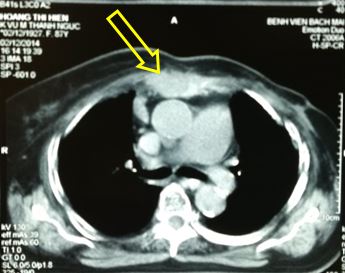

-          Sau 3 tháng điều trị xạ trị kết hợp Fulvestrant, trên lâm sàng bệnh nhân ổn định, hết đau ngực, u thành ngực thoái triển gần hết. Trên phim chụp CT ngực: khối u nhỏ lại, kích thước khoảng 2,5x1,5 cm (đầu mũi tên vàng)

Hình 2. Hình ảnh CT ngực sau điều trị 3 tháng: khối u nhỏ lại, kích thước khoảng 2,5x1,5 cm (đầu mũi tên vàng)